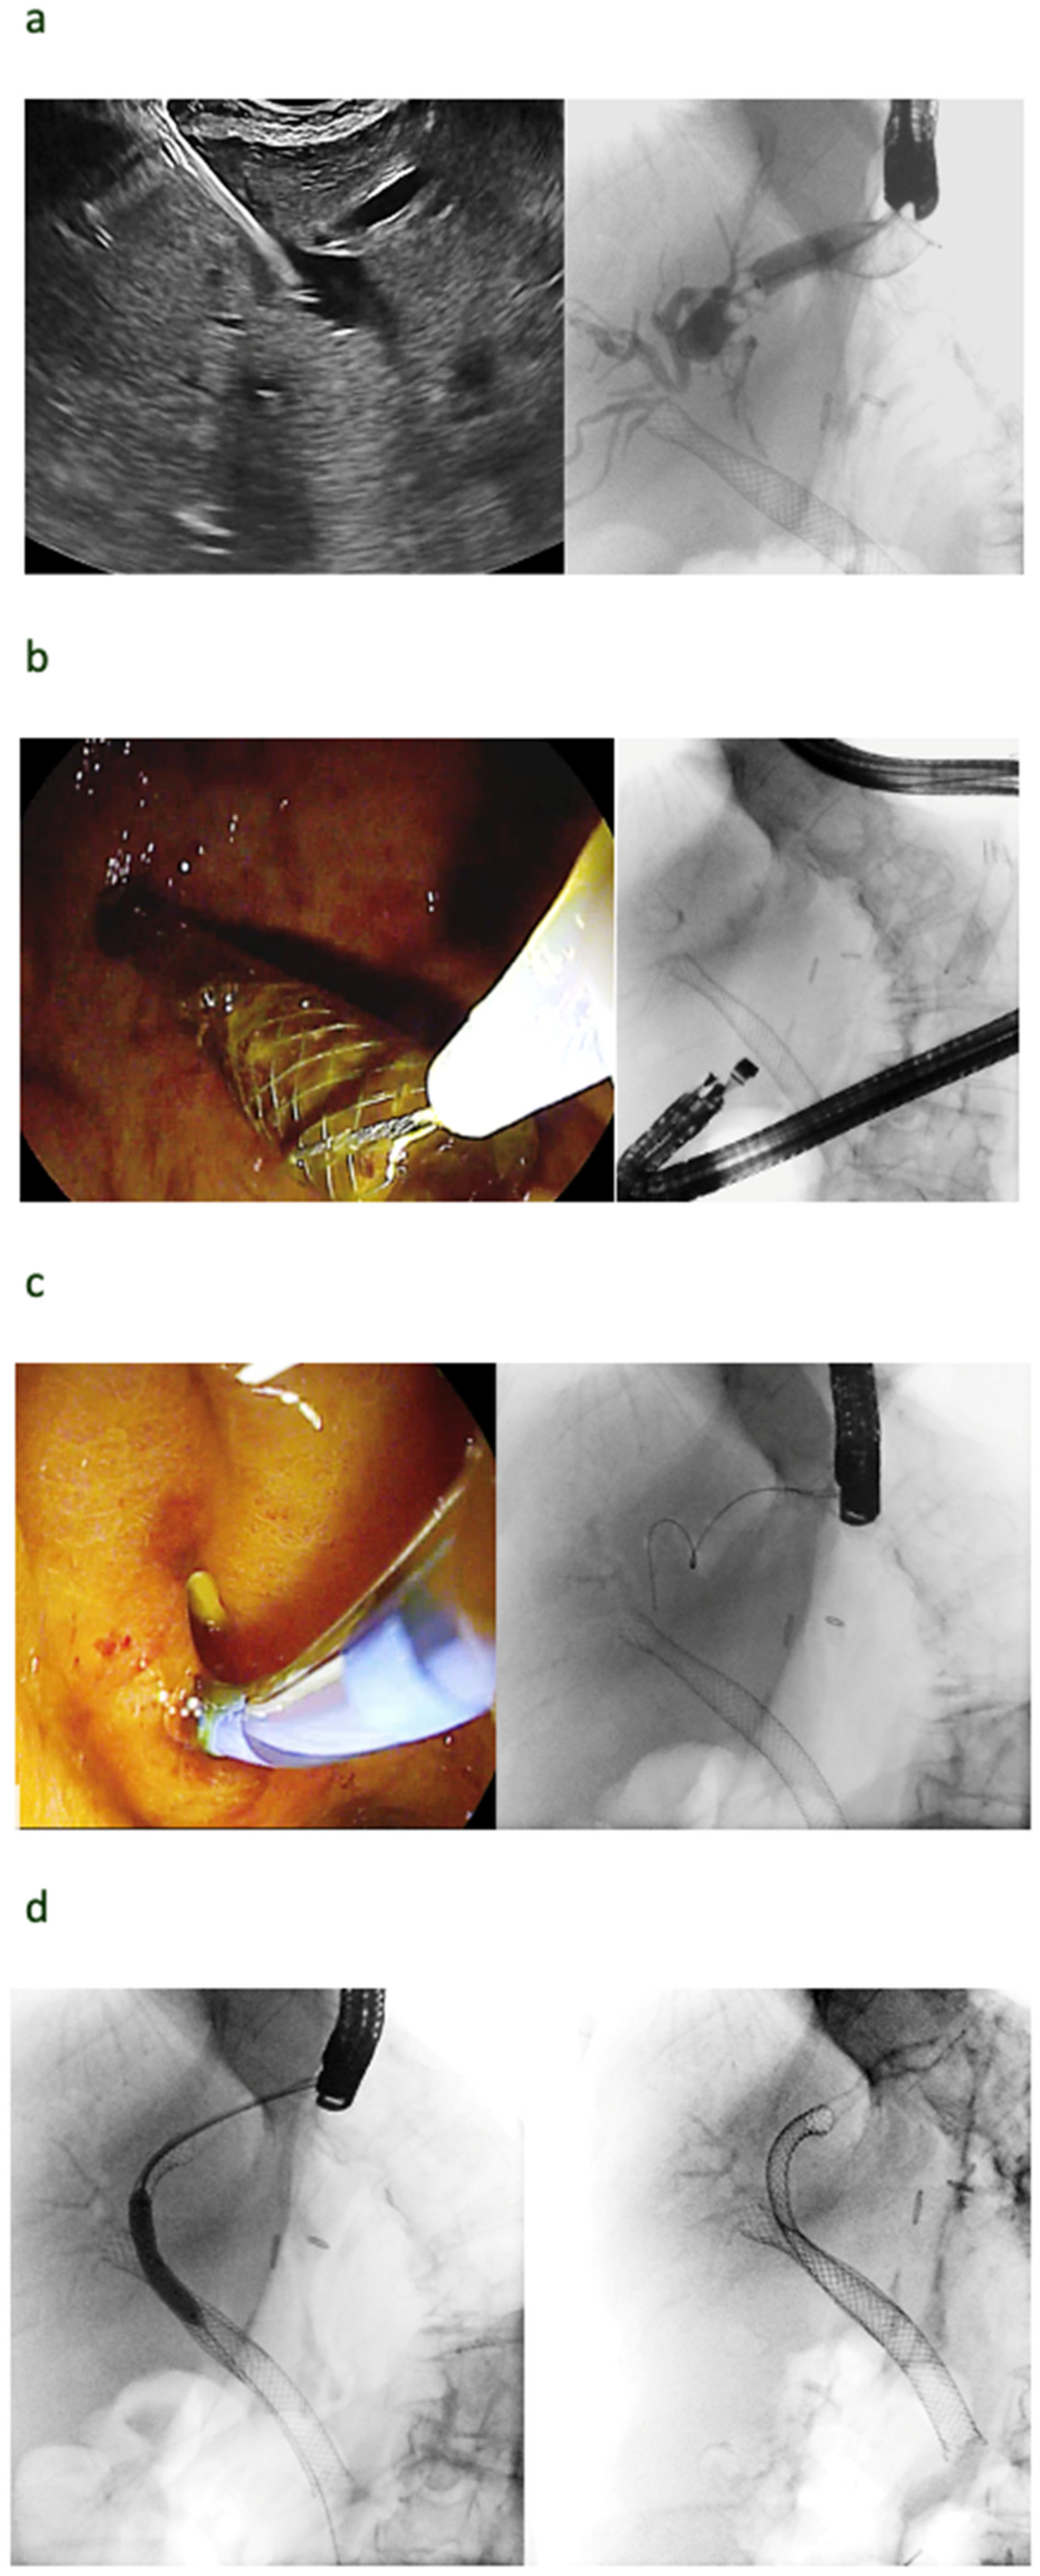

7. Do We Need Cystotomes?

8. Do We Need Bougies?

9. Are All EUS Needles the Same for EUS-BD?